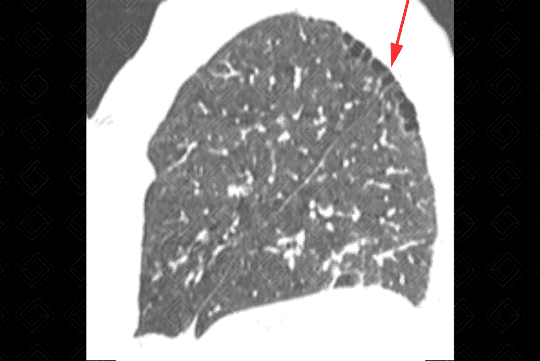

Texto alternativo para a imagem Figura 3. Créditos: Dra. Elazir Mota - Rio de Janeiro/RJ

Descrição das figuras 3, 4, 5 e 6: Tomografia computadorizada do tórax seguida de aquisições coronais, sagitais e axiais mostrando as extensas áreas de enfisema centrolobular dispersas pelo parênquima pulmonar (setas vermelhas).

• Tomografia computadorizada do tórax: Este método é mais sensível e específico que a radiografia de tórax na avaliação do enfisema. Tem sido empregado para detectar, quantificar e caracterizar a doença. A tomografia é capaz de diferenciar os vários tipos de enfisema, que pode ser classificado, de acordo com a região do ácino acometida, em proximal (centrolobular ou centroacinar - figuras 3, 4, 5, 6, 9, 10 e 11 ), distal (parasseptal - figuras 7, 8, 9, 10 e 11 ) ou todo ácino (panacinar ou panlobular).